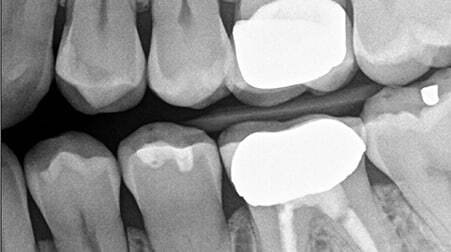

سنسور RVG چیست؟

RVG مخفف رادیو ویزوگرافی (Radio Viso Graphy) میباشد.

تکنیک RVG یک روش نسبتا جدید در تصویربرداری دندان میباشد که نیاز به فیلم رادیوگرافی، ظهور و ثبوت ندارد.

آروی جی جدیدترین نوآوری موجود در رادیوگرافی دیجیتال است و بالاترین وضوح تصویر را ارائه میدهد. سنسور RVG از یک حسگر تشکیل شده است.

سنسور RVG جایگزین فیلم های دندانپزشکی شده، و با تاباندن اشعهبه سنسور، این سنسور تصویر را بلافاصله بر روی سیستم متصل نمایش میدهد.

سنسور آر وی جی 142، با وجود فیلترهای ENDO و PERIO تصاویر با کیفیت و قابل تشخیصی ثبت مینماید. از فیلترها میتوان در جهت کاهش و افزایش کنتراست و همینطور شفافیت بیشتر برای تقویت تواناییهای تشخیص و مشاهدهی جزئیات استفاده نمود.